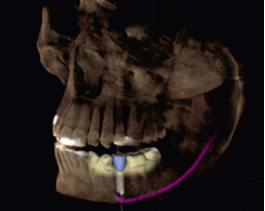

CGのインプラントソフトウェアは、神経管や骨格がビジュアル化され確認しやすく解剖学的な私見を必要とする患者様のインプラント治療に適したソフトウェアです。より正確なプランニングと埋入により安全性の確保を促し、不要なストレスが低減されます。治療状態を確認しインプラント埋入本数を増やすだけではなく、患者様へのプレゼンテーションにおいても3D画像により患者様への説明をサポートします。

正確な診断から生まれオペを確実なものにするサージガイド

サージガイドの作成

サージガイド